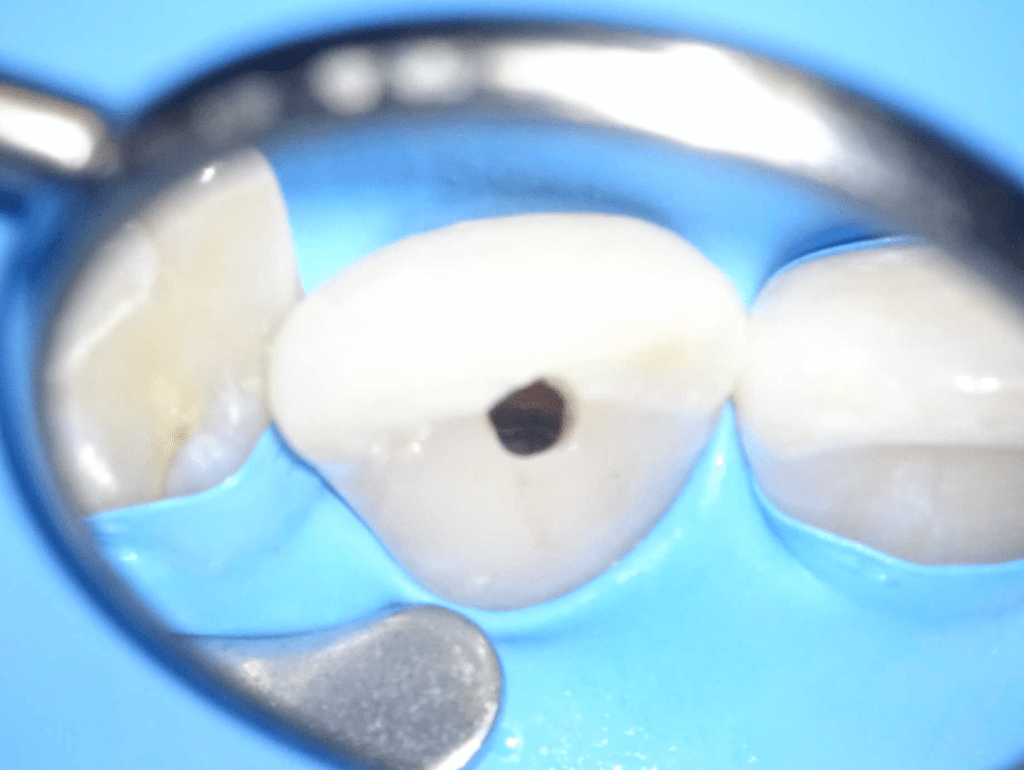

CALCIFICADOS

Premolar calcificado lesion